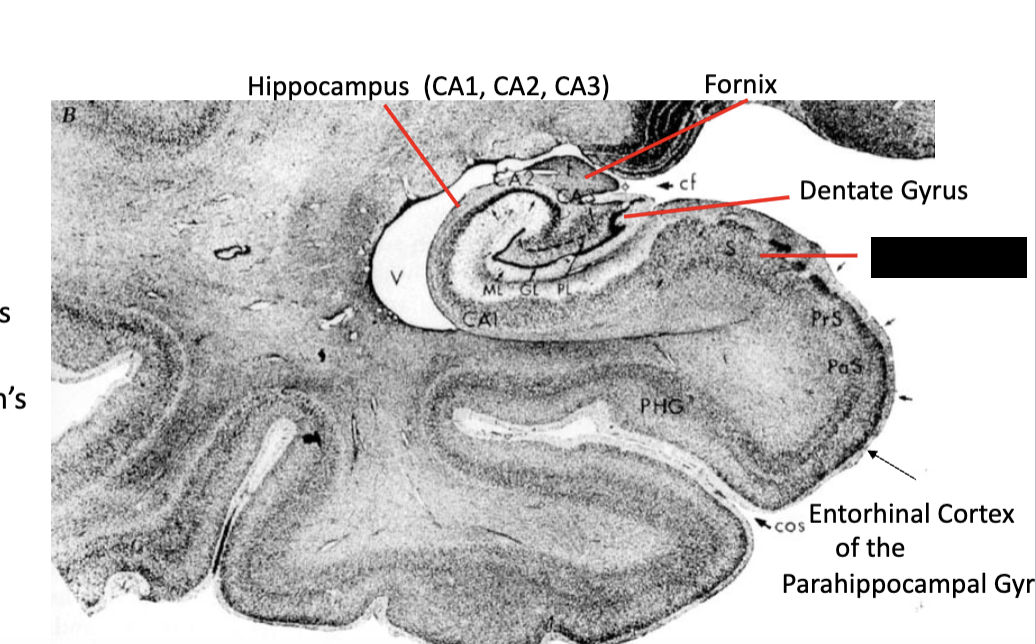

what are the three parts of the hippocampal formation?

dentate gyrus, hippocampus, and subiculum

dentate gyrus layers from superficial to deep?

molecular, granular, polymorphic

hippocampus layers from superficial to deep?

polymorphic, pyramidal, and molecular